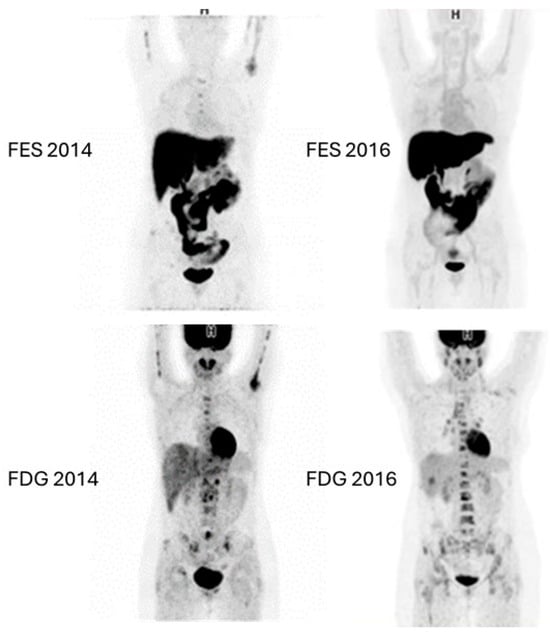

- van Kruchten, M.; Glaudemans, A.W.J.M.; Schröder, C.P.; de Vries, E.G.E.; Hospers, G.A.P. Positron emission tomography of tumour [18F]fluoroestradiol uptake in patients with acquired hormone-resistant metastatic breast cancer prior to oestradiol therapy. Eur. J. Nucl. Med. Mol. Imaging 2015, 42, 1674–1681. [Google Scholar] [CrossRef]

- Kurland, B.F.; Peterson, L.M.; Lee, J.H.; Schubert, E.K.; Currin, E.R.; Link, J.M.; Krohn, K.A.; Mankoff, D.A.; Linden, H.M. Estrogen receptor binding (18F-FES PET) and glycolytic activity (18F-FDG PET) predict progression-free survival on endocrine therapy in patients with ER+ breast cancer. Clin. Cancer Res. 2017, 23, 407–415. [Google Scholar] [CrossRef] [PubMed]

- Hao, W.; Li, Y.; Du, B.; Li, X. Heterogeneity of estrogen receptor based on 18F-FES PET imaging in breast cancer patients. Clin. Transl. Imaging 2021, 9, 599–607. [Google Scholar] [CrossRef]

- Gennari, A.; Brain, E.; De Censi, A.; Nanni, O.; Wuerstlein, R.; Frassoldati, A.; Cortes, J.; Rossi, V.; Palleschi, M.; Alberini, J.; et al. Early prediction of endocrine responsiveness in ER+/HER2-negative metastatic breast cancer (MBC): Pilot study with 18F-fluoroestradiol (18F-FES) CT/PET. Ann. Oncol. 2024, 35, 549–558. [Google Scholar] [CrossRef] [PubMed]